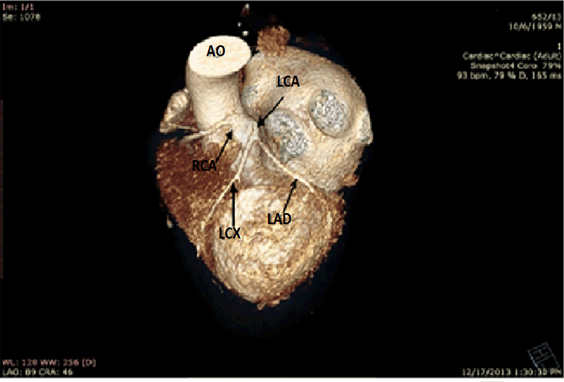

The origin and course of right coronary artery was abnormal and thus a CT angiography was performed. The CT angiography confirmed that the origin of the right coronary artery was from the left coronary sinus and that the artery coursed between the aorta and the pulmonary artery (Figure 3) and (Figure 4).

Figure 4: Computed tomography angiography reconstruction. Three dimensional view of coronary artery, origin. The origin of the right coronary artery is from the left coronary sinus. AO = Aorta; LAD = Left descending coronary artery; LCA = Left coronary artery; LCx = Left circumflex coronary artery. RCA = right coronary artery.